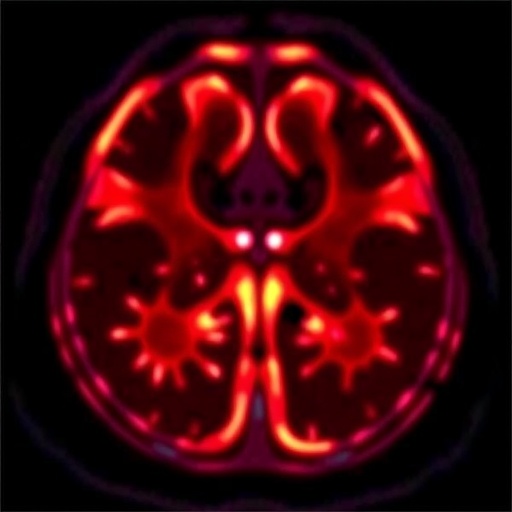

In a groundbreaking study set to redefine pediatric oncology, researchers have focused their attention on the potential of fluorodeoxyglucose positron emission tomography, commonly known as FDG PET imaging. This advanced imaging technique has shown great promise in the staging and prognostic assessment of pediatric lymphoma, a common type of cancer in children. By synthesizing existing data from various studies, this systematic review highlights the critical role FDG PET imaging plays in enhancing clinical outcomes for young patients battling this severe disease.

One of the most compelling aspects of FDG PET imaging discussed in the review is its ability to detect metabolically active tumor cells. Unlike conventional imaging, which may only reveal structural abnormalities, FDG PET detects areas of high glucose metabolism often indicative of malignancy. For pediatric patients, this characteristic is significant, as lymphomas may manifest differently than in adults, making traditional imaging less reliable. The ability to visualize these metabolic processes in real time offers a transformative shift in how oncologists assess the extent of the disease.